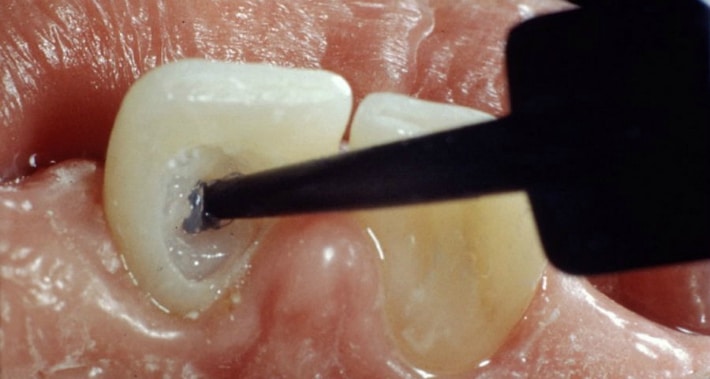

- На следующем этапе полость зуба вскрывается, а внутрь закладывается осветляющий гель.

- Для предупреждения вымывания депигментирующего состава проблемный зуб закрывается ватным шариком и временной пломбой из водорастворимого медицинского цемента, которую впоследствии легко удалить.

Для обеспечения максимально возможного контакта гелей с внутренней поверхностью зуба обязательно механически удаляются все остатки ранее поставленных пломб, а сам активный комплекс вносится посредством особого шприца-аппликатора.

Отбеливающим гелем заполняют коронковую часть зубной единицы и закрывают временной пломбой. Именно поэтому этот вид отбеливания еще называют внутрикоронковым или эндодонтическим. Для процедуры используется профессиональное отбеливающее средство на основе перекиси водорода, или перекиси карбамида, в концентрации 35%.

Пациенту надевают вакуум-формованную шину на отбеливаемую область. Для герметизации пломбировки корневого канала используют непроницаемую основу. Небольшое количество (размером с горошину) 10% перекиси карбамида наносят в полость доступа и соответствующую область шины с помощью шприца.